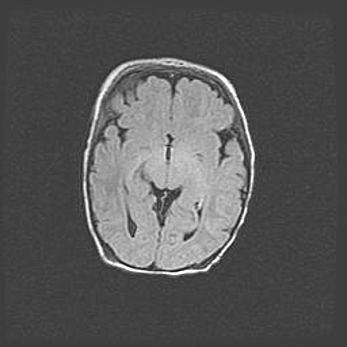

Наружная гидроцефалия с возможной атрофией височных областей.

Возраст: 28 дней

Вес: 3670 г

Пол: мужской

Окружность головы: 38 см

Срок гестации: 40 недель

Гидроцефалия головного мозга у новорожденных – это заболевание, которое характеризуется скоплением избыточного количества спинномозговой жидкости в желудочковой системе головного мозга в результате затруднения её перемещения от места выработки к месту поглощения в кровеносную систему или вследствие нарушения абсорбции. При открытой наружной форме гидроцефалии у новорожденных расширяются и переполняются субарахноидные пространства.

При нормотензивных  формах,  которые,  как  правило,  являются  следствием  перенесенных ишемических  повреждений  паренхимы  мозга,  возможно  сочетание микроцефалии  с нормотензивной гидроцефалией. В основе данных изменений лежит атрофия больших полушарий с преимущественной  локализацией  в  лобно-височных  областях.